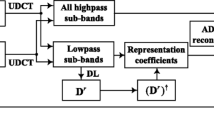

Recently, dictionary learning (DL) based methods have been introduced to compressed sensing magnetic resonance imaging (CS-MRI), which outperforms pre-defined analytic sparse priors. However, single-scale trained dictionary directly from image patches is incapable of representing image features from multi-scale, multi-directional perspective, which influences the reconstruction performance. In this paper, incorporating the superior multi-scale properties of uniform discrete curvelet transform (UDCT) with the data matching adaptability of trained dictionaries, we propose a flexible sparsity framework to allow sparser representation and prominent hierarchical essential features capture for magnetic resonance (MR) images. Multi-scale decomposition is implemented by using UDCT due to its prominent properties of lower redundancy ratio, hierarchical data structure, and ease of implementation. Each sub-dictionary of different sub-bands is trained independently to form the multi-scale dictionaries. Corresponding to this brand-new sparsity model, we modify the constraint splitting augmented Lagrangian shrinkage algorithm (C-SALSA) as patch-based C-SALSA (PB C-SALSA) to solve the constraint optimization problem of regularized image reconstruction. Experimental results demonstrate that the trained sub-dictionaries at different scales, enforcing sparsity at multiple scales, can then be efficiently used for MRI reconstruction to obtain satisfactory results with further reduced undersampling rate. Multi-scale UDCT dictionaries potentially outperform both single-scale trained dictionaries and multi-scale analytic transforms. Our proposed sparsity model achieves sparser representation for reconstructed data, which results in fast convergence of reconstruction exploiting PB C-SALSA. Simulation results demonstrate that the proposed method outperforms conventional CS-MRI methods in maintaining intrinsic properties, eliminating aliasing, reducing unexpected artifacts, and removing noise. It can achieve comparable performance of reconstruction with the state-of-the-art methods even under substantially high undersampling factors.